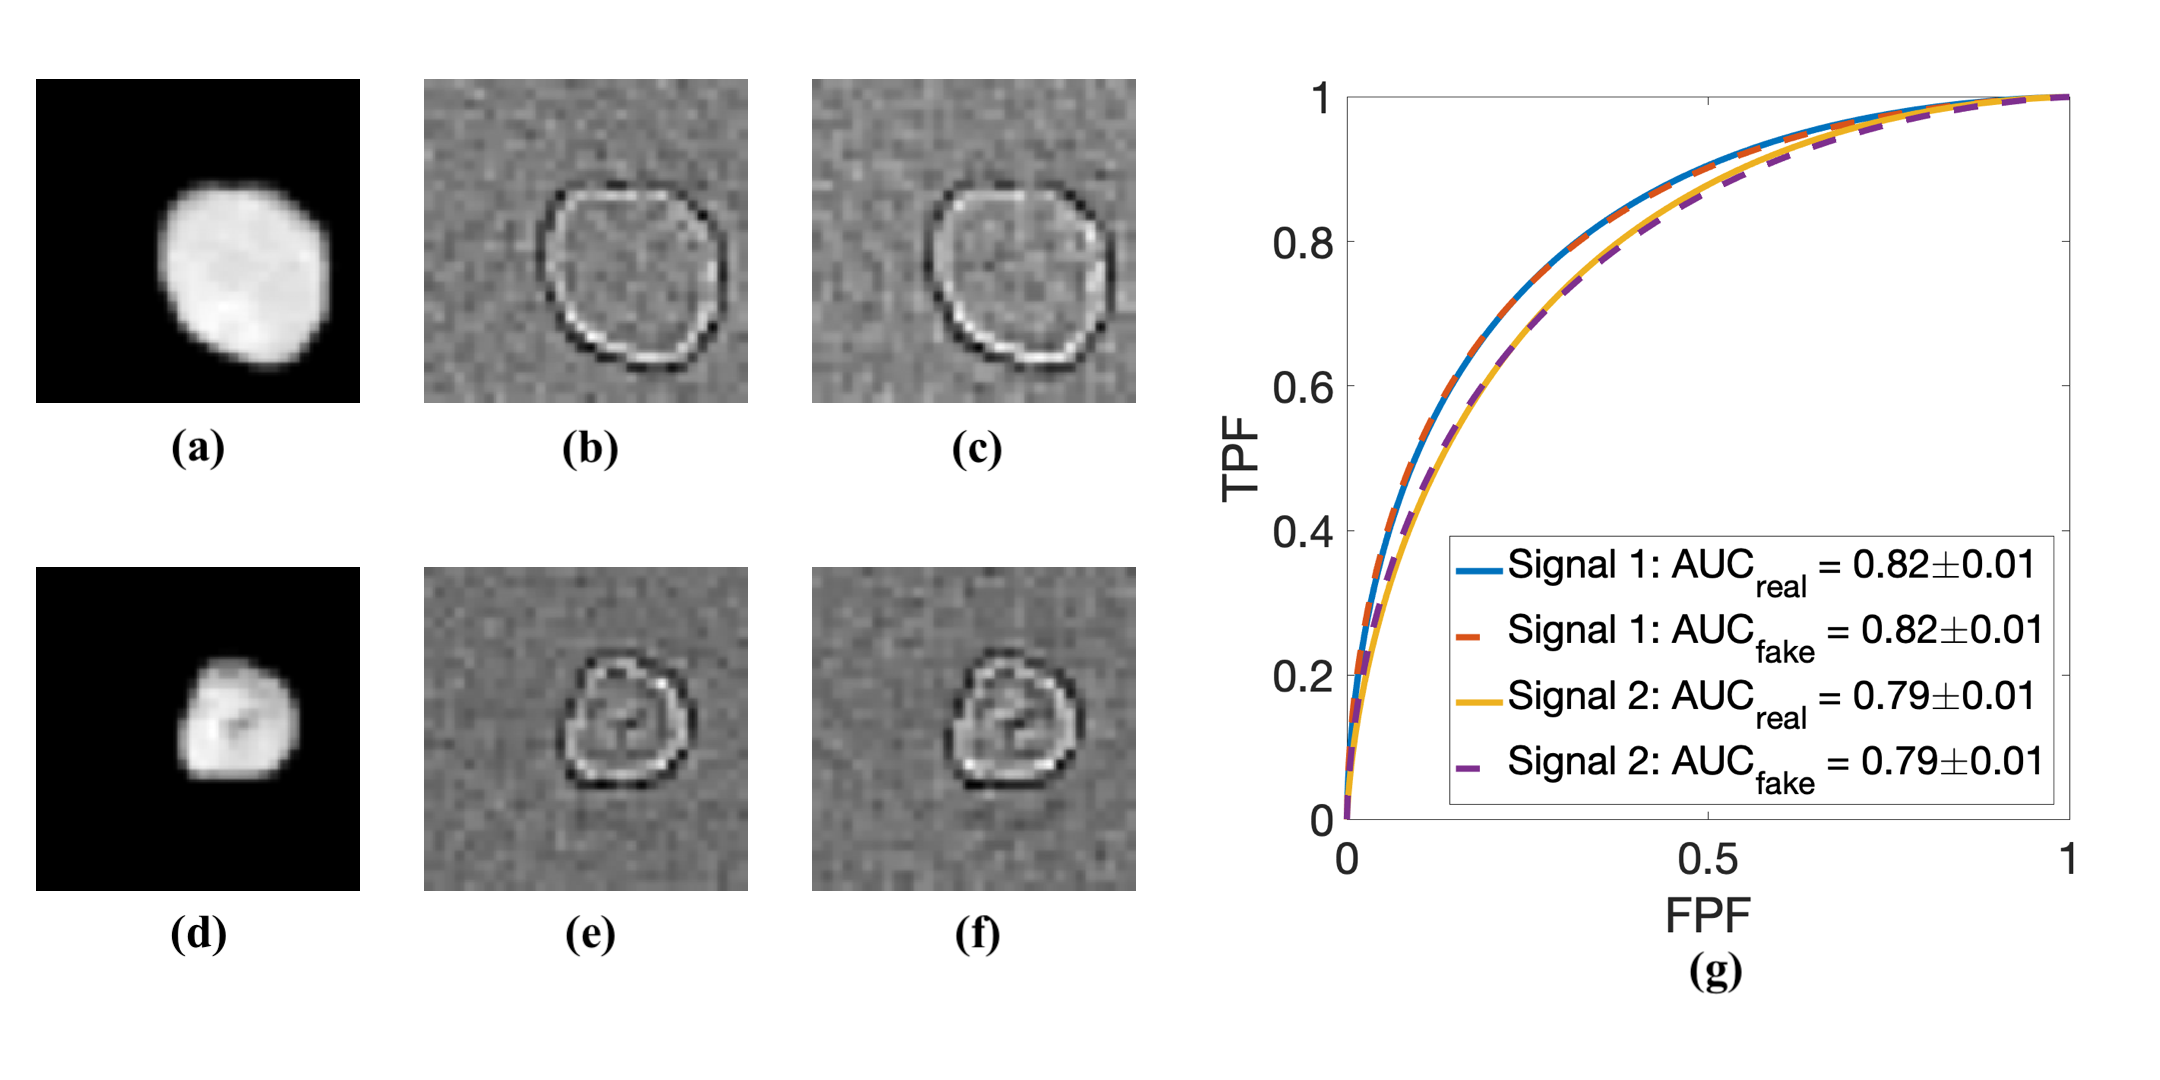

where denotes the signal to be detected, and is independent and identically distributed Gaussian noise. Two different signals represented by two artificial tumors were considered. These signals are shown in Fig. 3.

The signal detection tasks were performed on a region of interest (ROI) that was centrally located in the images. The ROIs had dimension of . The covariance matrices corresponding to the real and ProAGAN-produced images were computed by use of 3000 ROIs extracted from the real and ProAGAN-produced images, respectively. These covariance matrices were subsequently employed to computed the Hotelling observer (HO) by use of a covariance matrix decomposition[1]. The performances of the HOs were evaluated on a testing dataset that comprised 500 pairs of signal-absent and signal-present images. The receiver operating characteristic (ROC) curves and AUC values corresponding to the ProAGAN-produced images were compared to those corresponding to the real images. The ‘proper’ binormal model[15] was employed to fit the ROC curves.

The Hotelling templates that were computed by use of the real images and the ProAGAN-produced images are compared in Fig. 6. The ROC curves and AUC values corresponding the real images and the ProAGAN-produced images are compared in Fig. 6 (g), in which the solid curves and the dashed curves correspond to the HOs computed by use of real images and synthetic images produced by the ProAGAN, respectively. The ROC curves are almost identical.